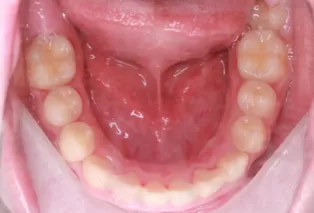

Photos intra-orales